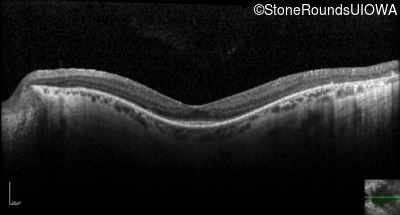

Visit at age: 51 years

Optical Coherence Tomography - Right - 20/50

Exemplar / OCT Stack